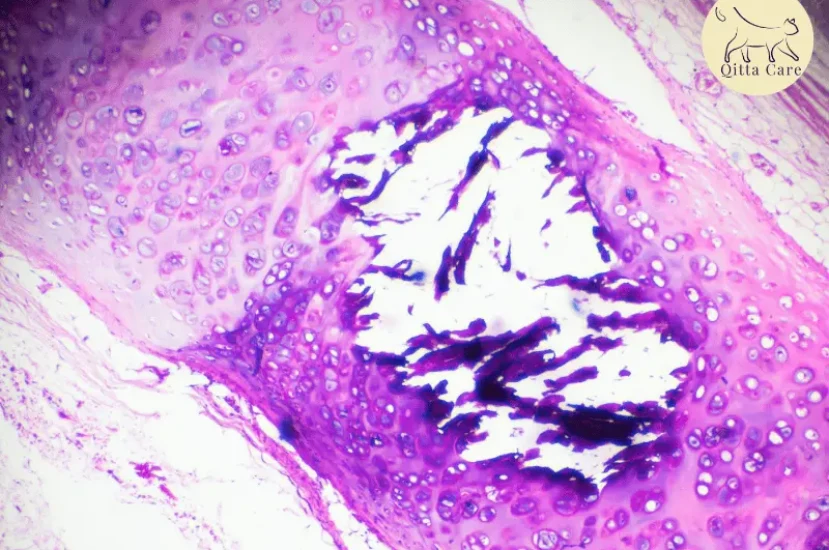

كيف يتم تشخيص الجلطات الدموية في الرئتين عند القطط؟

يعتمد التشخيص على الفحص السريري، بالإضافة إلى الأشعة السينية، الأشعة المقطعية (CT)، وتحاليل الدم. في بعض الحالات، يتم استخدام تخطيط القلب أو تخطيط الصدر لتحديد مكان الجلطة.